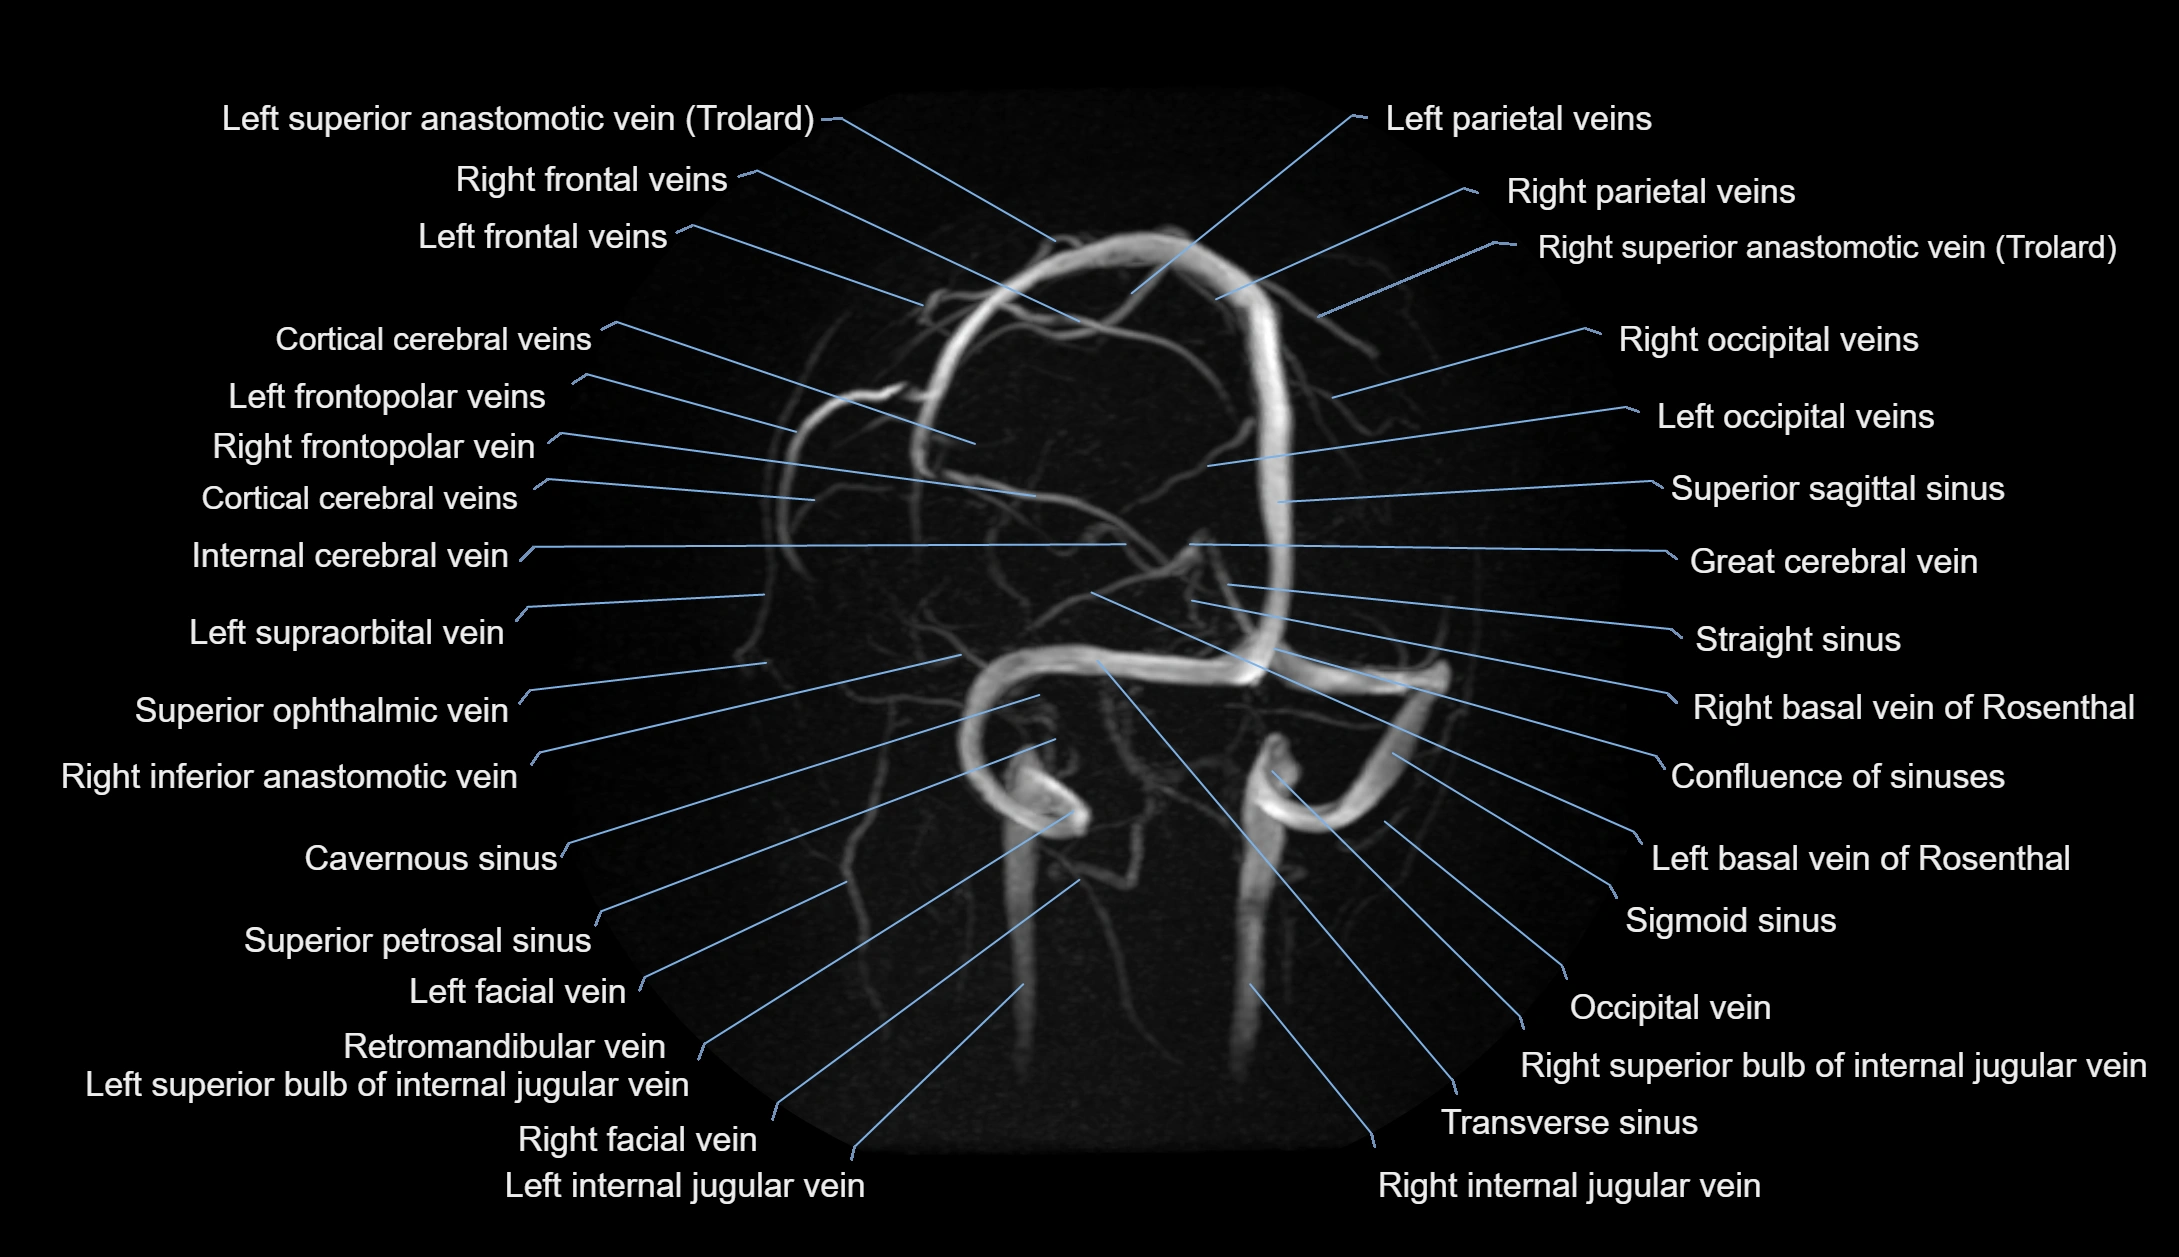

MR Venography (MRV):

• Time-of-flight (TOF) or contrast-enhanced MRV shows the angular vein as a bright enhancing venous channel

• Clearly demonstrates its continuity with the facial vein and superior ophthalmic vein

• MRV is highly useful in evaluating thrombosis, venous obstruction, or collateral venous drainage